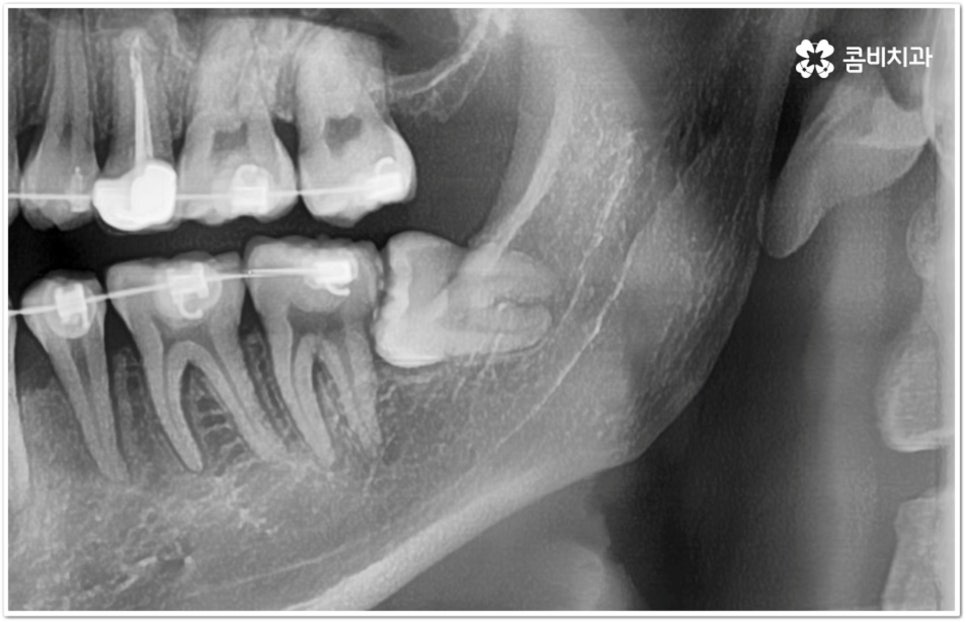

만약 똑바로 자라나고 관리가 용이하며 마주보는 대합치 역시 정상적으로 맹출되었다면 사랑니를 꼭 발치할 필요는 없을 거예요. 그러나 보통 사랑니는 사람의 치아 중에 가장 마지막에 나오는 치아라서 이미 구강 내 공간이 비좁은 상태이기 때문에 비스듬하게 자리를 잡고 일부분만 맹출이 되는 경우가 많이 있어요. 보통 머리가 앞쪽으로 기울어진 근심위로 자리잡는 케이스가 가장 많으며 그 밖에도 치아 머리가 뒤쪽으로 기울어져 있거나 혀쪽, 볼쪽으로 누운 케이스, 아예 옆으로 완전히 누운 케이스 등도 발견되고 있는데요.

잇몸에 반쯤 덮힌 채로 삐뚤게 나온 사랑니는 칫솔질을 제대로 하기 어렵고 위생 관리가 잘 되지 않아 주변 잇몸에 염증이 생기기 쉬우며 어금니까지 충치가 번질 위험이 높아지게 되어 구강 건강 관리 및 예방 차원에서 발치 처치를 해주실 필요가 있어요. 발치 난이도는 사랑니의 경사 각도와 방향 및 치아 뿌리의 길이와 개수, 사랑니 뒤쪽 턱 뼈의 각도 및 형태, 하치조 신경 또는 상악동까지의 거리 등에 따라서 달라질 수 있습니다.

이때 아래사랑니발치 의 경우 아래턱 부근을 지나가는 큰 신경인 하치조 신경을 건드리지 않고 조심스럽게 사랑니만 제거해야 하기 때문에 3D-CT 등 정밀 검진 기계를 통해 사랑니의 매복 위치, 깊이, 각도 등의 상태와 신경까지의 거리 등을 먼저 꼼꼼하게 파악한 후에 발치를 해 줄 필요가 있는데요. 만약 완전히 매복되어 있다면 사랑니 주변에 함치성 낭종이 발생할 수도 있는데 이로 인해 주변 치조골이 파괴되고 어금니 쪽으로 병변이 확산되면 결국 치아를 상실하게 되거나 턱뼈가 약해져서 작은 충격에도 부러지는 현상이 발생할 가능성도 있으므로 될 수 있는대로 치료 시기를 놓치지 않는 것이 중요한 포인트라고 할 수 있어요.

이와 같이 환자분들의 상황에 따라서 잇몸 절개 및 골삭제 후 사랑니를 조각내어 빼내야 하는 고난도의 과정들이 필요할 수도 있기 때문에 아래사랑니발치 시 관련 임상 경험이 많고 섬세한 기술력을 가지고 있는 숙련된 의료진과 함께 하시길 권유드리고 있습니다.

아래사랑니발치 와 다르게 윗 사랑니 발치 시에는 상악동까지의 거리가 너무 짧을 경우 천공 및 감염의 위험이 있으니 이에 대해서 3D CT 를 통해 꼼꼼하게 확인하고 환자분들의 상황에 맞는 치료를 진행할 필요가 있어요. 예를 들어 사랑니로 인한 문제가 크지 않은 경우 그대로 두고 지켜볼 수도 있고 다른 치료를 하는 중에, 즉 교정이나 임플란트 등을 진행하는 과정에서 발치가 꼭 필요한 경우라면 상악동 거상술, 뼈이식 등의 치료를 선행하여 무리하지 않게 뽑아주는 것이 좋을 거예요.